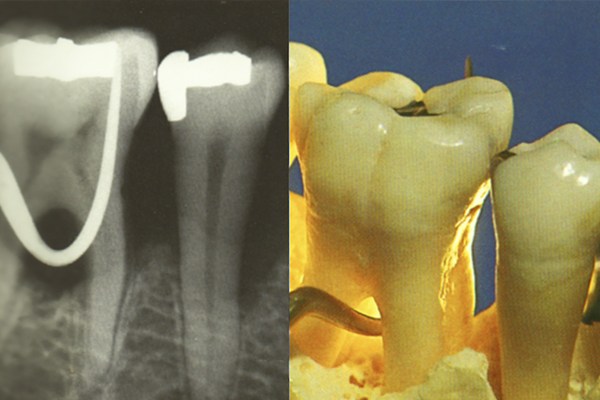

A principal causa para o aparecimento de doenças periodontais é a acumulação de placa bacteriana no sulco gengival, causando uma inflamação crónica que, se não for tratada atempadamente, pode levar a que os dentes comecem a abanar, podendo até cair.

É uma área que engloba tratamentos de rotina como as destartarizações, curetagens e alisamentos radiculares, e tratamentos mais avançados através de técnicas de microcirurgia periodontal, recobrimentos radiculares, enxertos gengivais, alongamentos coronários, regeneração óssea e gengival.